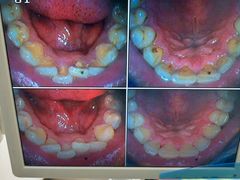

• 圣贝口腔(海淀店)

• -圣贝口腔(海淀店)